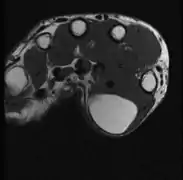

A physical exam is typically the easiest way to diagnose it. Rarely, a tissue biopsy or imaging may be required. The imaging modality of choice is magnetic resonance imaging (MRI) because it has superior sensitivity of distinguishing it from liposarcoma as well as mapping the surrounding anatomy.[22]